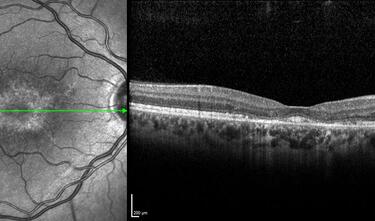

Clase 3 - Más allá de la interopretación de OCT estructural papilar. Correlación histológica

Clase 18 - Signos estructurales diferenciales entre neurodegeneración y exudación en DMAE